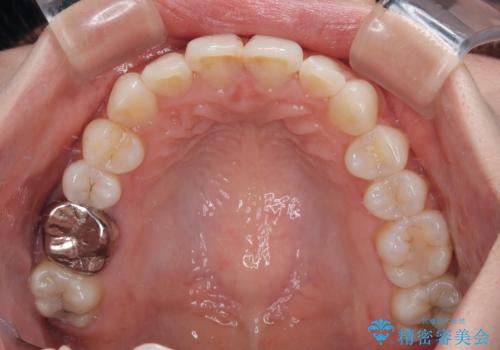

- 上下前歯のデコボコを改善したいとのことで来院された患者様です。

マウスピースを長時間装着し続ける自信はあまりないとのことでしたが、目立たない装置であれば頑張って装着するとのことで、インビザラインによる矯正治療を行うこととしました。

初めの1年くらいは何とか頑張って装着してくださいましたが、途中から変化をあまり感じられなくなり、日々の装着時間は徐々に短くなってしまいました。

前歯のデコボコはもっと改善できましたが、3年半が経過し、初診時と比べたら大幅に良くなったとのことで終了することとなりました。